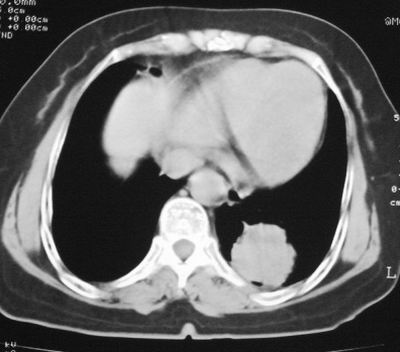

患者,女,64岁,4年前左腮腺"多形性"腺瘤手术治疗史.现复查胸部ct见左下肺块状影,该影与原左腮腺手术是否有联系?

表现:胸廓左右对称,气管居中,两肺野纹理增多,左下肺见一高密度影,周围见纤维条索影,心影及肺门无增大,双肋膈角锐利,横膈未见异常。

本次复查胸部ct

左下肺软组织块影,有分叶、毛刺、空泡及胸膜牵拉征,左下肺周围性肺癌。

左肺下叶周围型肺癌,支持!(软组织肿块+分叶+毛刺+空泡+胸膜凹陷征)

左下肺后基底段实性肿块,周围有毛刺,病变周围有肺气肿,与降主动脉间有条带状影相连,病灶4年前查体发现,纵隔内未见肿大淋巴结。考虑.肺隔离症,建议增强扫描与周围型肺癌鉴别。